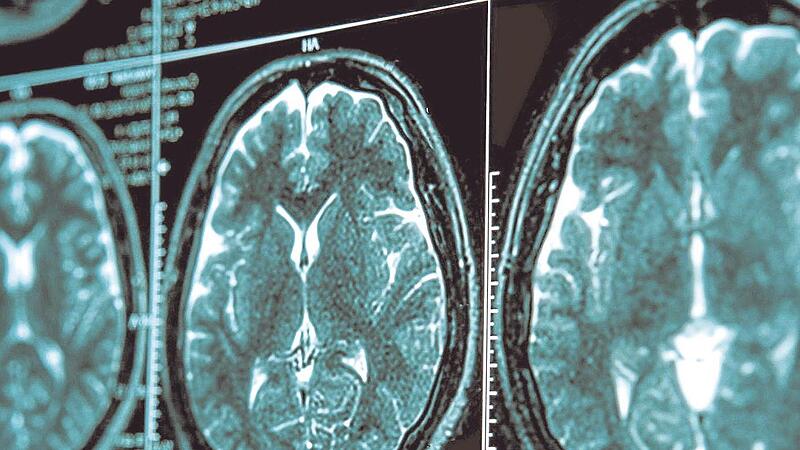

Ein Leben mit Parkinson

– Die unheilbare Gehirnerkrankung trifft immer mehr Menschen. Ein Mann aus Bayern erhielt die Diagnose schon mit 50 Jahren. Er erzählt. Ein Schritt hat seine Lebensqualität erhöht.